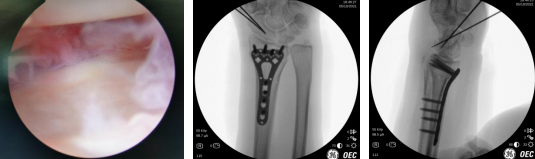

当天,齐伟亚主任手术团队为患者李阿姨进行了“关节镜辅助下左桡骨远端骨折复位内固定术+舟骨骨折复位内固定术”。关节镜辅助下复位桡骨远端骨折端,在左腕掌侧做一1.5公分的切口,放置1块金属接骨板,C臂透视见骨折对位、对线良好,关节镜再次探查,见关节面对位平整,依次对位缝合修复皮下组织。闭合复位左舟骨,术中透视见骨折对位、对线良好,内固定在位。手术顺利。

术中